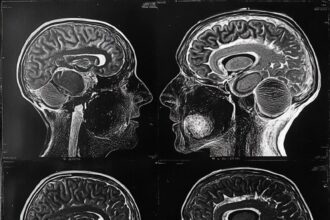

This revelation represents just the tip of an intellectual iceberg that’s been hiding in plain sight. Modern neuroscience has shattered one of psychology’s most enduring myths: that babies enter the world with minds as empty as fresh notebooks, ready to be filled with whatever their environment provides.

But here’s what researchers have discovered in the last two decades: babies are born with remarkable cognitive abilities that challenge everything we thought we knew about human development.

This isn’t hyperbole or parental wishful thinking. Research suggests that infant brains are in what scientists call a “hyperplastic” state—extraordinarily flexible and capable of making neural connections that adult brains simply cannot. They can learn multiple languages simultaneously without confusion, adapt to radically different environments, and process information in ways that would overwhelm mature minds.

The traditional view has it backward. Instead of empty vessels waiting to be filled, babies are more like supercomputers running complex programs we’re only beginning to understand. Their apparent helplessness masks sophisticated information-processing capabilities that rival—and in some cases exceed—adult cognition.